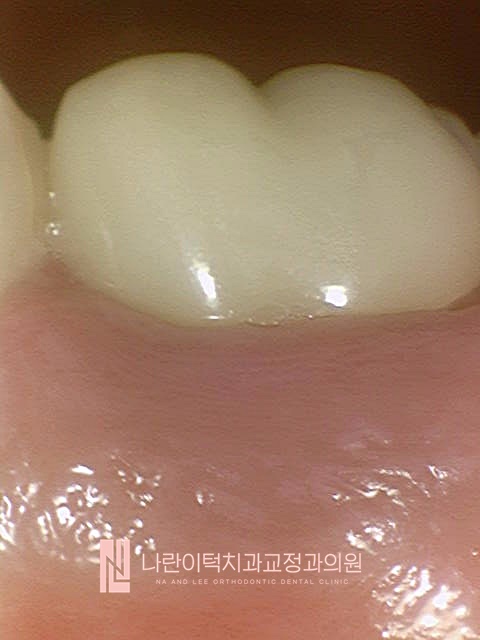

초진 구강내 사진 Intra-oral photo

#36치아 잇몸도 비교적 건강하시고, 지르코니아 보철도 잘 세팅되어 있었습니다.